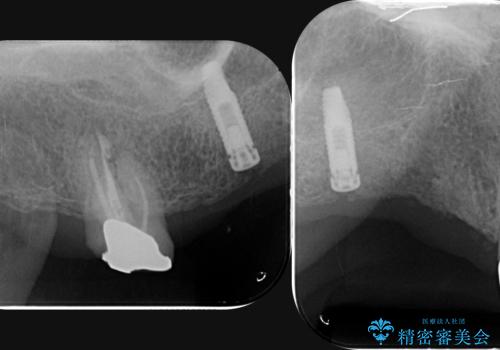

- 他院で1本インプラントを入れたまま治療に通うことができなくなり、途中からの治療を希望され来院されました。

既に埋入されているインプラントは位置が悪いのでそのまま骨内に留置することとし、新たに咬合機能を回復すべく3本のインプラントを埋入すると同時に吸収した骨幅を増やし、安定してインプラントで噛める環境整備を目指します。

インプラントが長持ちするために、インプラント周囲の十分な骨量・角化歯肉の存在・安定した咬合を一つづつ整備する治療を行いました。